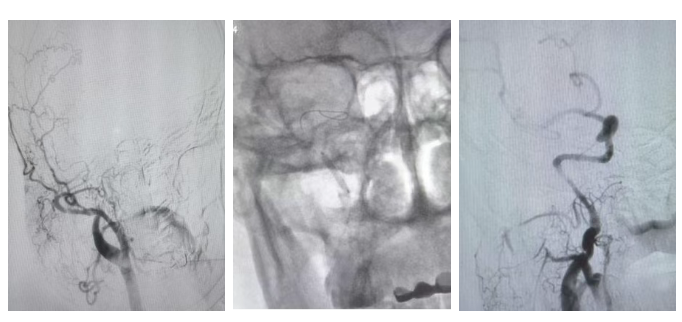

当意外突发、急症来袭,我院神经外科团队24小时待命,始终坚守在守护生命的第一线。近日,团队成功为一名外省来兰务工的51岁男性患者实施“急性颈内动脉闭塞再通术”,以极速响应诠释了“时间就是大脑”的救治理念。患者王先生(化名),51岁,因“突发左侧肢体失灵、失语并伴意识障碍2小时”,急诊就诊于我院。急诊科与神经外科团队第一时间启动卒中绿色通道,迅速完成颅脑CT检查及采血检验,排除脑出血。诊断为:1.脑血管闭塞性脑梗死 2.急性脑血管闭塞3.偏瘫。在黄金时间窗内,医护团队高效配合,立即为患者进行静脉溶栓,桥接血管内治疗。排除手术禁忌后,团队为患者迅速行脑血管造影,造影见右侧颈内动脉闭塞,术中采用导管抽吸、血管成形术等神经介入技术,顺利复通重度狭窄基础上急性闭塞的右侧颈内动脉,术后复查脑血管造影见血流恢复满意,脑组织重新获得血流灌注。

术后患者意识即刻恢复清醒,左侧上下肢肌力Ⅳ+级,双眼凝视消失,语言恢复正常。此次成功救治,充分体现了神经外科团队在脑血管病急危重症领域的快速响应及救治能力。